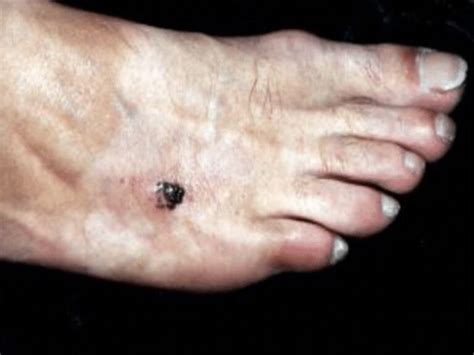

Melanoma Lentiginoso Acral

Melanoma lentiginoso acral en el pie